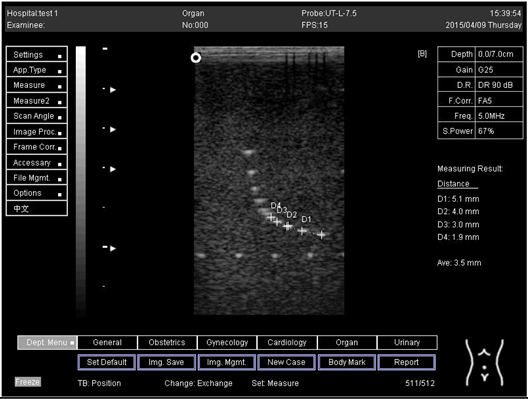

24.0Axial resolution

Biomimetics 07 00130 i029

D1 = 5.0

D2 = 4.1

Lateral resolution

Biomimetics 07 00130 i030

D1 = 4.8

Table A4. The distance for axial and lateral resolution in mm for depth of 5.0, 6.0, 7.0 and 9.0 cm depth for flat probe at surface 4.